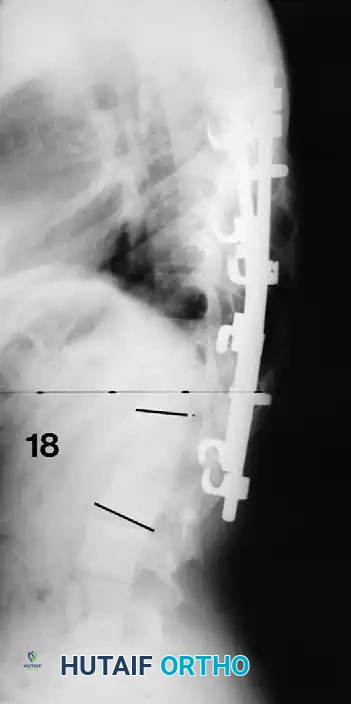

Associated Surgical & Radiographic Imaging